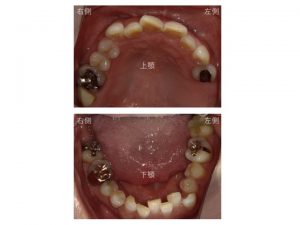

初診時の口腔内が以下です。

上顎左右奥歯に2箇所(上顎右側一番奥歯は被せ物が取れたままです)、

下顎左右奥歯に3箇所

金属が入っています。